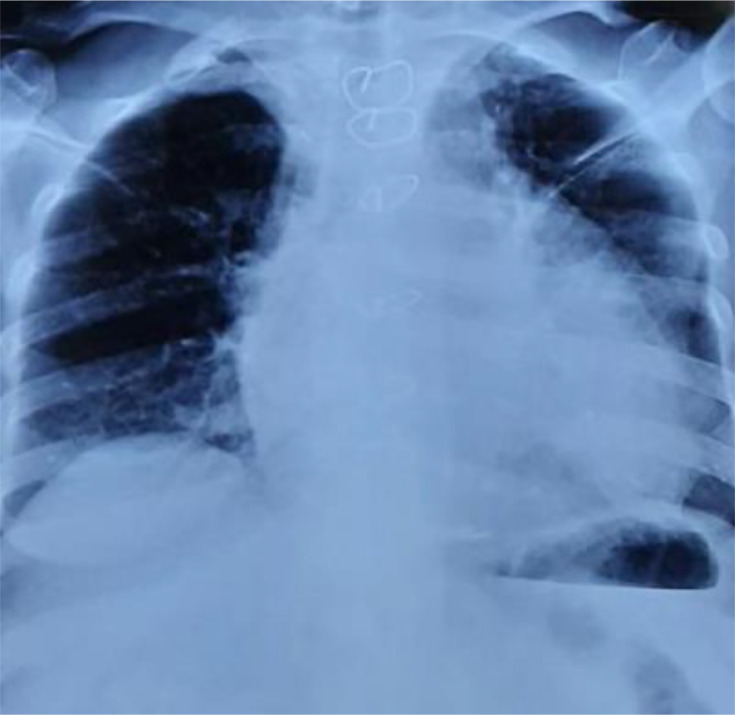

Tuberculosis remains a major public health issue in Morocco. Pulmonary tuberculosis is the most common form, but various extrapulmonary forms exist. Tuberculous pericarditis is a rare form of extrapulmonary tuberculosis that can be complicated by cardiac tamponade, pericardial constriction or their combination, which can threaten the patient's life. Its clinical and radiological signs are nonspecific, and the clinical presentation can be misleading and incomplete, sometimes even with an initial tamponade. We report the case of a 68-year-old female patient admitted for intense retrosternal chest pain associated with acute dyspnoea, evolving in the context of unquantified weight loss and general deterioration. Additionally, she reported a history of fever and night sweats. Clinical examination revealed a conscious, febrile, hypotensive, tachycardic, polypneic patient with good oxygen saturation, signs of right heart failure and muffled heart sounds on auscultation. Chest X-ray revealed cardiomegaly, and the ECG showed diffuse low voltage. Given the presence of Beck's triad suggestive of cardiac tamponade, a transthoracic echocardiogram was performed, revealing a large pericardial effusion with a 'swinging heart'. A chest CT scan also confirmed the large pericardial effusion. The diagnosis of cardiac tamponade was made based on the clinical and radiological findings, and pericardial drainage was performed, after which the patient showed clinical improvement. PCR GenXpert MTB/RIF Ultra detected the presence of Mycobacterium tuberculosis in the pericardial fluid, with no resistance to rifampicin. Culture was positive for M. tuberculosis. The diagnosis of tuberculous pericarditis was, thus, confirmed, and the patient was started on quadruple antituberculosis therapy with good clinical progress.